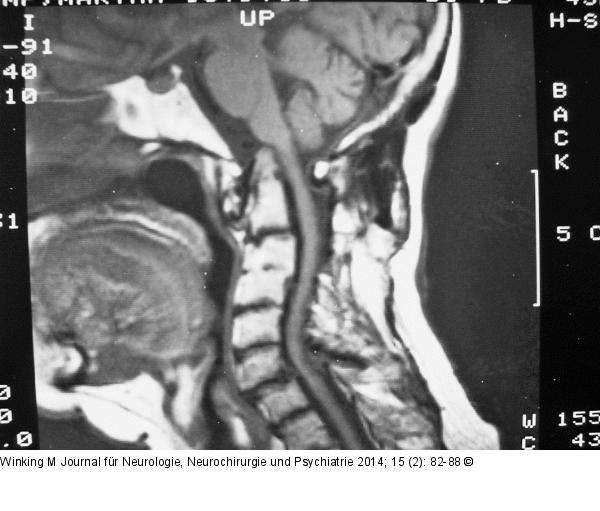

Abbildung 2: Rheumatische Wirbelsäule Sagittales T2-MRT mit Vertikalluxation des Dens. |

Sagittales T2-MRT mit Vertikalluxation des Dens. |